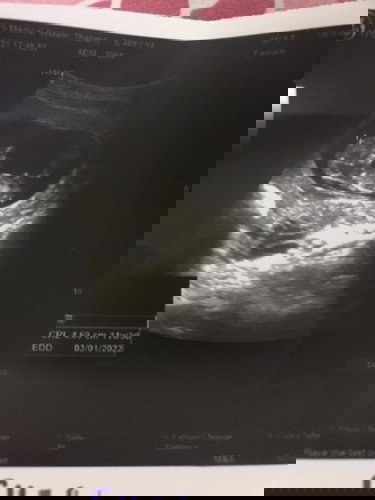

อั ล ต รา ซ า ว ด์

อายุครรภ์11w3d ค่ะ แต่เด็กเป็นตัวชัดเจนมาก มีแม่ๆคนไหนซาวต์แล้วชัดแบบนี้บ้างค่ะ #ท้องแรกจ้า

อายุครรภ์เท่ากันเรยค่ะ..เพิ่งไปหาหมอมาวันนี้ก้อชัดเหมือนกันค่ะ

ับ้านนี้เห็นชัดเหมือนกันค่ะ ซาวด์ตอน11w